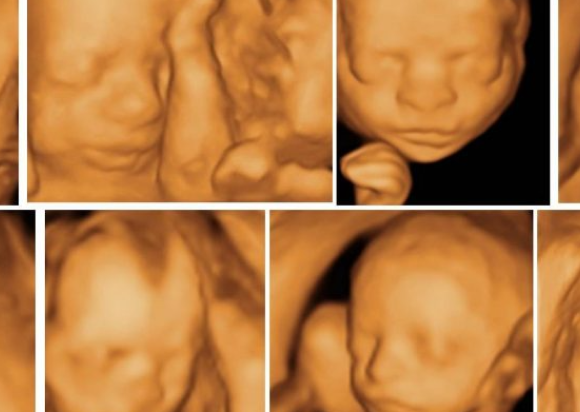

Our specialized team of doctors at ASMEE performs tests on the fetus to screen for health problems, presides over ultrasound examinations, and attempts to treat birth defects, disorders, and infections. Facilities like 4D ultrasonography, amniocentesis, etc helps in early detection and timely intervention helping the delivery of a healthy baby.

Anomaly scan is a detailed ultrasound of baby when it is approx. 20 weeks old. The aim is determined whether baby is anatomically normal or not.